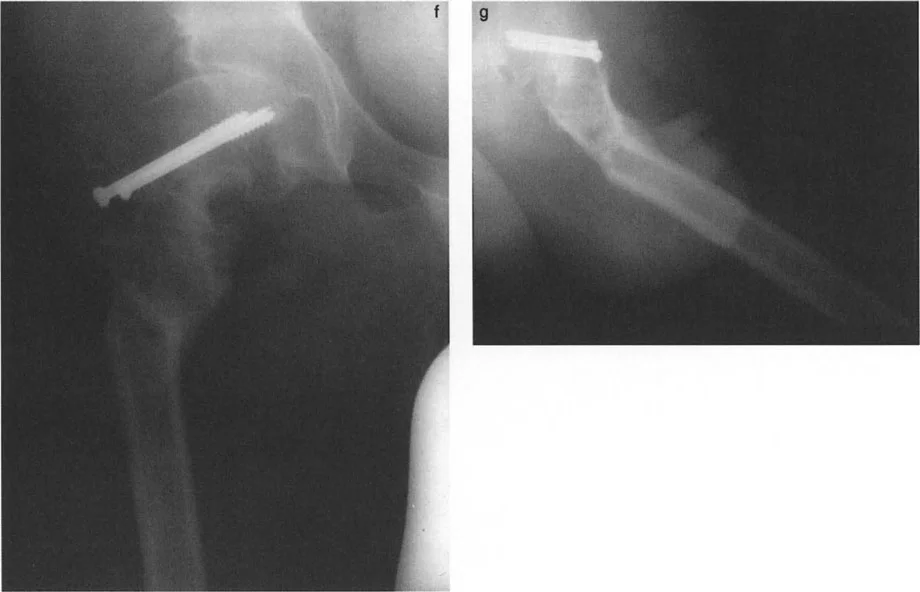

يُعد فهم العلاقة بين مركز دوران الانحراف (CORA) ومستوى قطع العظم أمرًا بالغ الأهمية.

- قاعدة قطع العظم 1: إذا تم إجراء قطع العظم بالضبط عند مستوى CORA، فإن تصحيحًا زاويًا فقط (بفتح أو إغلاق وتد) يكون مطلوبًا. يتم استعادة المحور الميكانيكي، ولن يحدث أي إزاحة لقطعي العظم.

- قاعدة قطع العظم 2: إذا كان CORA يقع قريبًا (أو بعيدًا) عن المستوى الفعلي لقطع العظم، فيجب إزاحة الجزء البعيد لاستعادة المحور الميكانيكي. سيؤدي التقويم الزاوي البحت عند مستوى بعيد عن CORA إلى تشوه إزاحة ثانوي.

نظرًا لأن CORA يقع قريبًا من خط قطع العظم، فإن الإزاحة إلزامية تمامًا أثناء التصحيح:

* لتشوهات الانبساط (التي تتطلب قطع عظم للانثناء): يجب إزاحة عمود الفخذ للأمام.

* لتشوهات الانثناء (التي تتطلب قطع عظم للانبساط): يجب إزاحة عمود الفخذ للخلف.

سيؤدي الفشل في إزاحة عمود الفخذ بشكل مناسب إلى تشوه إزاحة ثانوي، مما يُغير المحور الميكانيكي للطرف السفلي (انحراف المحور الميكانيكي - MAD) وقد يسبب ميلان خط المفصل عند الركبة.